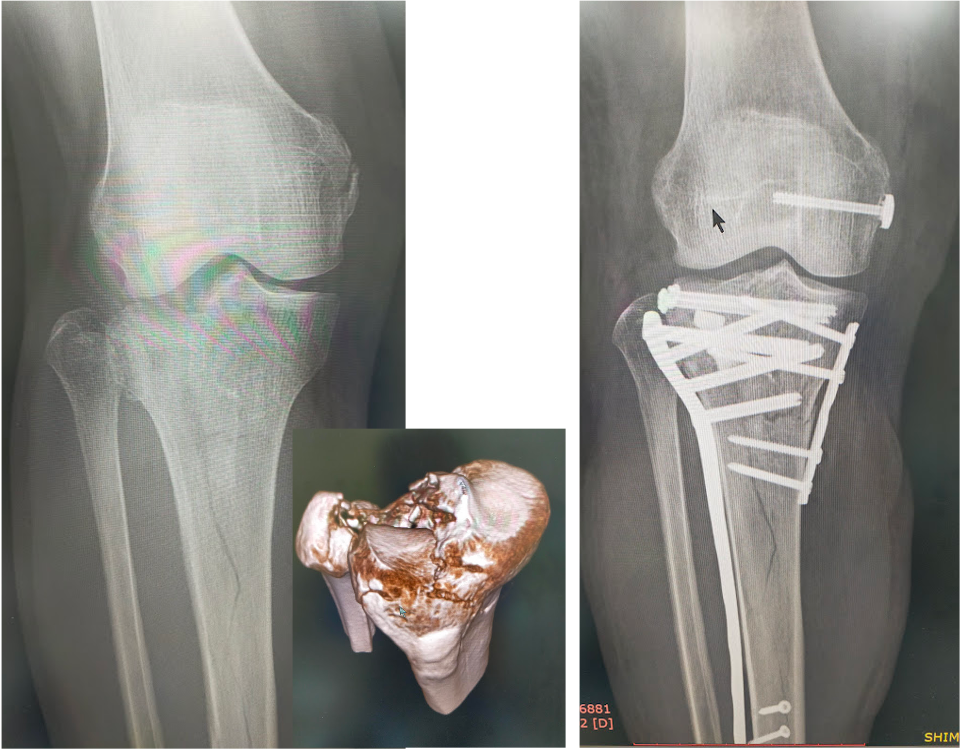

関節を含む骨折は、機能障害を起こしやすく、正確に関節を再建する必要があり、早期リハビリ、機能改善にはとても重要です。

脛骨近位端骨折に対する骨接合術